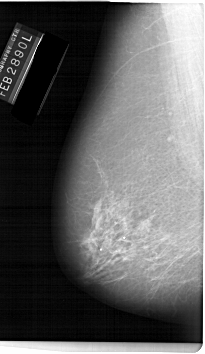

A_1144_1.LEFT_CC

LEFT_CC LINES 6631 PIXELS_PER_LINE 4201 BITS_PER_PIXEL 12 RESOLUTION 43.5 NON_OVERLAY